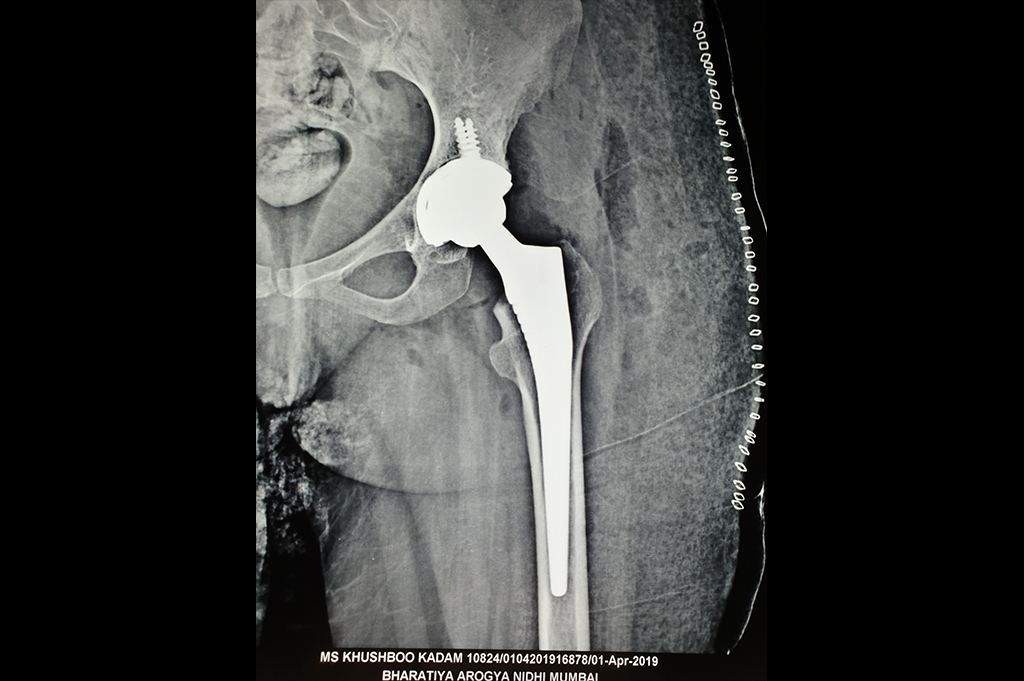

Total Hip Replacement - THR